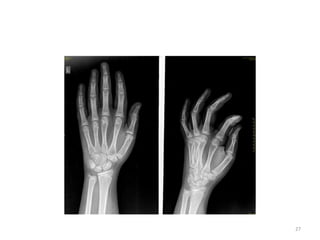

24

BONE

(hand)

OSSIFICATION

CENTRE

APPEARANC

E

CONJOINT

EPIPHYSIS

FUSION/U

NION

First Metacarpal 2-3 - 15-17

Proximal phalanges 1.5-2 - 15-18

Metacarpals 2-3 -

15-19

Middle phalanges 2-4 - 15-18

Distal phalanges 2-4 - 15-18

BONE (hand) OSSIFICATION CENTRE APPEARANC E CONJOINT EPIPHYSIS FUSION/U NION First Metacarpal 2-3- 15-17 Proximal phalanges 1.5-2 - 15-18 Metacarpals 2-3 - 15-19 Middle phalanges 2-4 - 15-18 Distal phalanges 2-4 - 15-18 25